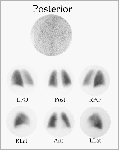

Una gammagrafía de perfusión normal se caracteriza por la distribución uniforme del radiotrazador en ambos pulmones. Un resultado como el de la imagen es un buen indicador de una buena prognosis y los enfermos dentro de esta categoría no necesitan anticoagulantes. En casos como este, el diagnóstico es claro.